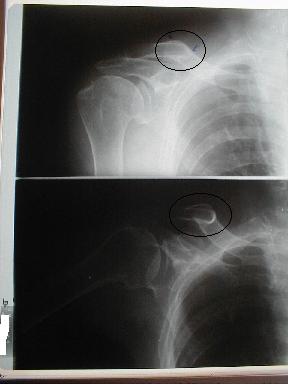

症例6

右鎖骨骨折

86歳 女性

負傷年日 平成10年10月11日

負傷原因 自宅の物干し場で上を見上げて洗濯物を干していてフラフラとなり、転倒負傷

10月24日受傷13日目

当初さほどに痛みを感じなかったので我慢していたが、徐々に肩に違和感を訴え我慢できず来院レントゲン検査したところ骨折を認める

皮下溢血,腫脹,圧痛